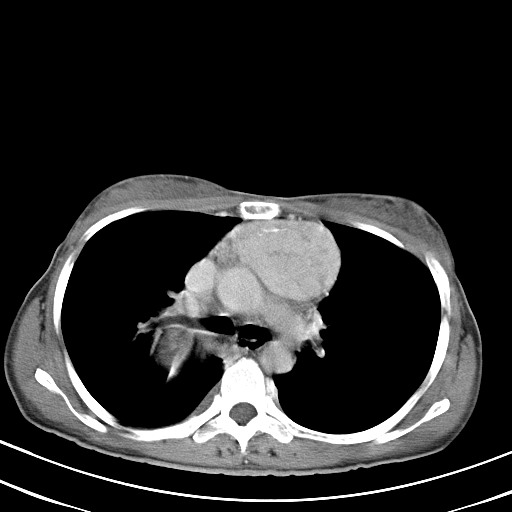

以下是引用汪涛同志在2007-8-2 0:40:00的发言:[br]病变虽然广泛,同时侵及双侧纵隔,但是无论左侧和右侧上下观察都是与右侧颈部甲状腺相延续的,而且强化幅度基本一致,又同时具有恶性病变病变的某些特征:肿块过大且密度不均,部分层面与正常纵隔结构分界不清,结合病史已有两年,考虑:胸内甲状腺肿恶变可能。[br]